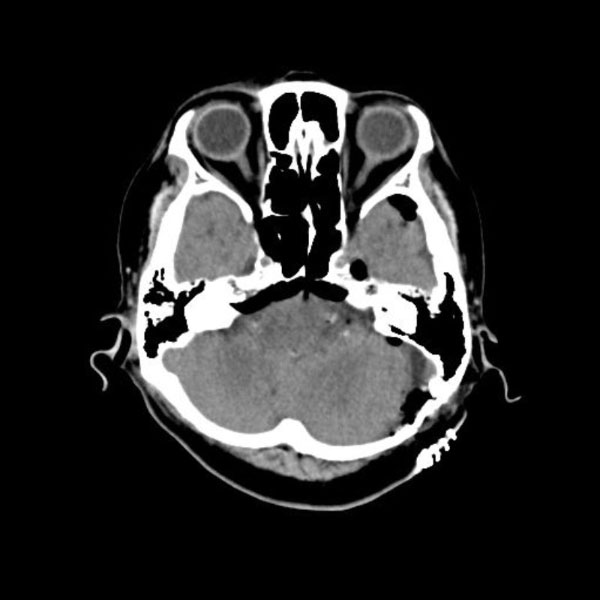

手術前

(MR1)

手術後

(CT)